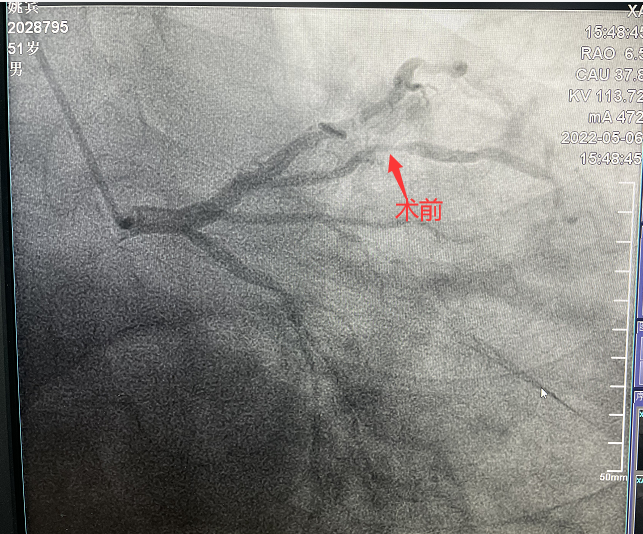

患者,51歲,男性,入院診斷為:冠心病、不穩定型心絞痛。冠狀動脈造影顯示對角支90%狹窄病變。對于該類患者,通過介入治療(PCI)方式早期干預相關血管可明顯減輕患者癥狀,減少死亡率、并發癥,改善患者的預后。在醫生與患者及家屬溝通時,患者家屬提到,他們了解得知臨床有一種新型的可吸收支架,置入體內后能完全被降解和吸收,患者及家屬希望能用這種新型的支架進行手術治療。由于生物可吸收支架有著嚴格的適應癥,因此經過嚴格評估,最終對患者進行了Xinsorb生物可吸收支架(BRS)置入術。支架植入術后,經IVUS檢查,支架貼壁良好,結果完美,手術順利結束。

手術造影圖